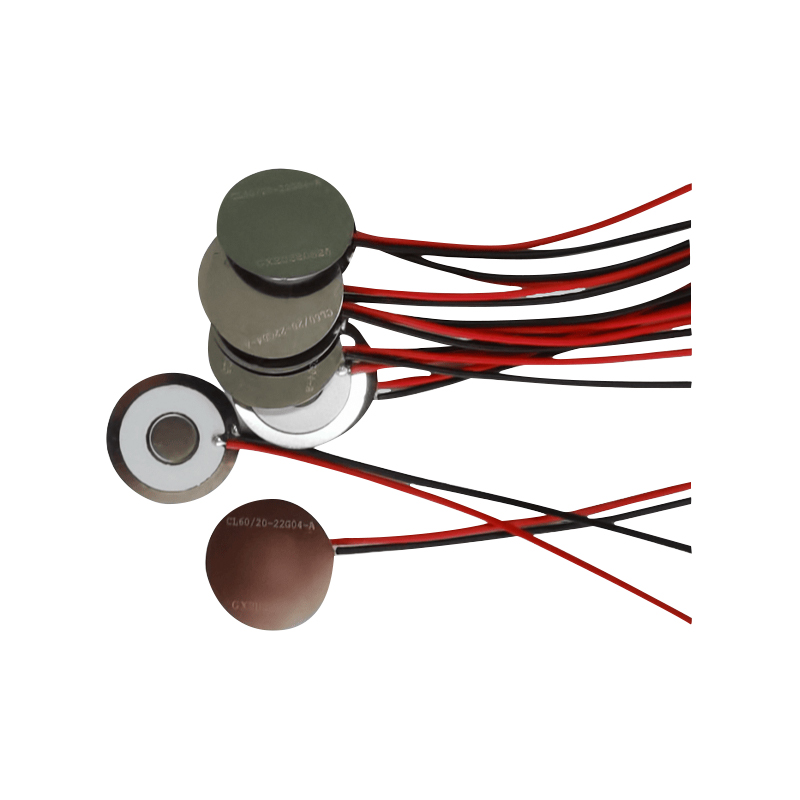

Le compresse di nebulizzatore a rete medica sono componenti di precisione utilizzati nei dispositivi medici per convertire farmaci o soluzioni in minuscole particelle di aerosol per il trattamento di vari disturbi respiratori come l'asma e la broncopneumopatia cronica ostruttiva (BPCO), ecc. mediante inalazione. Il design e la scelta dei materiali del foglio del nebulizzatore sono fondamentali per garantire un'efficace somministrazione del farmaco e il comfort del paziente. Il foglio del diaframma inossidabile viene perforato con migliaia di minuscoli fori a rete da 2-3 μm nella lamiera di acciaio attraverso la tecnologia di perforazione laser in un processo laser di precisione, quindi è strettamente legato al foglio rotondo in ceramica piezoelettrica, che converte la frequenza di risonanza del foglio piezoelettrico in energia di vibrazione ad alta frequenza attraverso il segnale di uscita della scheda driver PCB e si rompe rapidamente il farmaco liquido in fini particelle di aerosol. Queste goccioline sono anche chiamate dimensione mediana delle particelle, quando la percentuale mediana delle particelle D50 raggiunge >60% o più, le particelle saranno abbastanza piccole da poter raggiungere in profondità i polmoni fino alla superficie degli alveoli con la respirazione, migliorando così l'efficienza di assorbimento del farmaco e l'effetto terapeutico. Il foglio per nebulizzatore a micro rete Medical Mesh ha principalmente diverse forme, il foglio per nebulizzatore a micro rete in acciaio inossidabile, il foglio per nebulizzatore medico al nichel palladio, il foglio per nebulizzatore medico in polimero PI e così via. Tutto quanto sopra avviene attraverso la conversione dell'energia di vibrazione ceramica piezoelettrica per ottenere l'effetto di atomizzazione.

La ceramica piezoelettrica senza piombo è conosciuta come la "perla" dell'industria piezoelettrica, il futuro sostituirà gradualmente la ceramica piezoelettrica a base di piombo in tutti gli aspetti, che ha già le stesse prestazioni piezoelettriche, e il foglio piezoelettrico a base di piombo. È completamente atossico, innocuo, sicuro ed ecologico, non contiene piombo, antimonio e altri metalli pesanti e altri elementi soggetti a restrizioni Rohs, elevata temperatura Curie Tc-328 ° C, perdita elettrica molto bassa TangentLoss Pertanto, il chip di atomizzazione medica piezoelettrica senza piombo ha un grande valore commerciale e un valore universale, la ceramica piezoelettrica senza piombo veramente atossica e rispettosa dell'ambiente, oltre alle prestazioni piezoelettriche non inquinanti e commisurate alla ceramica a base di piombo, diventerà una popolare ceramica piezoelettrica rispettosa dell'ambiente. Dopo anni di ricerca e sviluppo, dopo continui test e sperimentazioni, l'azienda è riuscita a realizzare il chip di atomizzazione medica senza piombo per ottenere la stessa quantità di atomizzazione del chip di atomizzazione a base di piombo e gli stessi requisiti di particelle di diametro. Il chip nebulizzatore a rete medica senza piombo, sicuramente brillerà e otterrà una vasta gamma di scenari di utilizzo.